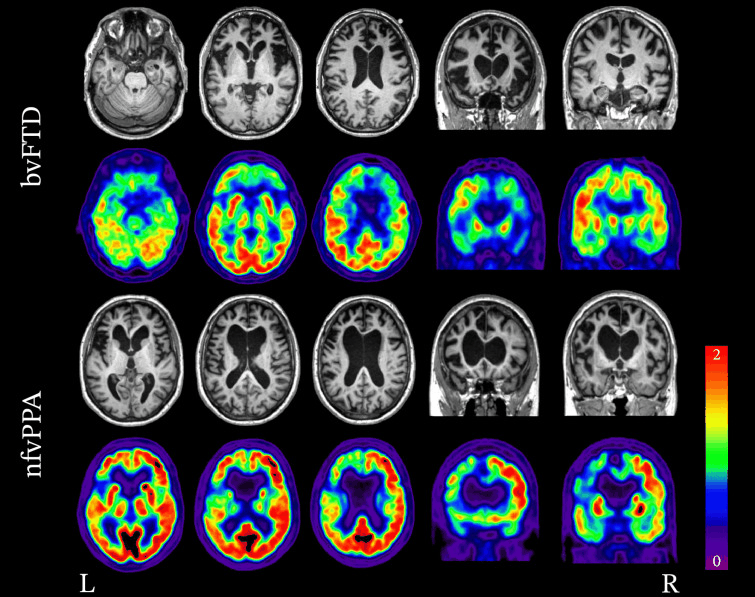

Neuroimaging patterns associated with behavioural variant FTD (bvFTD) and nonfluent variant primary progressive aphasia (nfvPPA). Structural MRI and FDG-PET demonstrating the variability in patterns of atrophy and hypometabolism in FTD. In the case of bvFTD, significant bilateral frontal lobe atrophy and hypometabolism is seen. In the case of nfvPPA, atrophy and hypometabolism is lateralised and is greatly impacting the left frontal lobe more so than the right.

Peet BT et al. Neurotherapeutics 2021 Apr; 18 (2): 728-52; used with permission